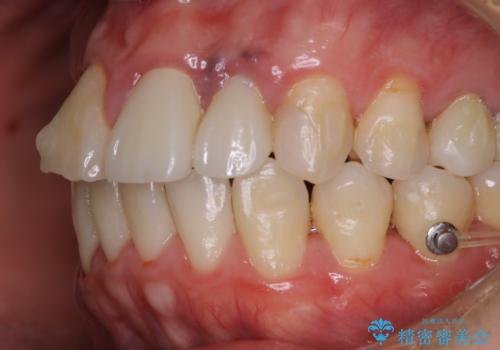

インビザライン治療中には、歯の表面にアタッチメント(効率的に歯の移動をするもの)を設定します。そのため歯ブラシでは届きにくい細かい部分などに、歯石や着色がついてしまうことがあります。着色などを放置していると、着色なのか、虫歯なのかの判別もしずらく正確にお口の中の状態を診断できません。

矯正治療中も定期的に歯科医院にてPMTCを受けて、お口のケアを行うことをおすすめします。